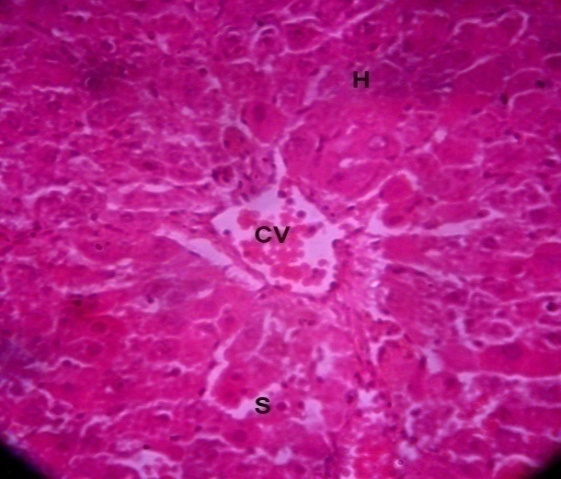

Histopathological examination

The present study is also done to study histopathological alterations in the rat liver, whose autopsy was done after the treatment of 7, 14, and 21 d. Fig. 1 shows a normal histoarchitecture of the liver with a clear CV, H, and S. Fig. 2 shows the structure of the liver after 7 d of treatment with the standard drug (Silymarin). The present study is also done to study histopathological alterations in the rat liver, whose autopsy was done after the treatment of 7, 14, and 21 d. Fig. 1 shows a normal histoarchitecture of the liver with a clear CV, H, and S. Fig. 2 shows the structure of the liver after 7 d of treatment with the standard drug (Silymarin). The CV is filled with RBC and damaged cells, and a fatty layer surrounds the CV, but the fat layer is thinner than that of rats treated with other formulations (fig. 3). With the treatment of Formulation-II, more damage was seen than with Formulation-I and the standard drug. CV is filled, and a thick fatty layer is present around CV. Hseem to be damaged, and S seem to be dilated due to hepatocellular damage (fig. 4). Whereas rats were treated with Formulation-III, hepatocellular damage was clearly seen. CV filled with damaged blood cells and surrounded by thick fatty layer inflammation in H was also clearly visible here; due to which S are compressed (fig. 5). In the experimental group, H seem to be more damaged than in other groups, where some air filled space was also observed due to hepatocellular damage. A fatty layer surrounds the CV, and vast damage was also noticed (fig. 6).

Fig. 1: Showing the normal histoarchitecture of the control rat liver with a clear CV and a normal arrangement of H and S (H and E stain 100X).

Fig. 1: Normal control |

Fig. 13: After 21 d in the control rats, the normal histoarchitecture was visible with the proper arrangement of H and CV (H and E stain 100X).

Fig. 13: Normal control |